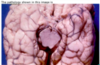

The image shows deep brain stimulation to control Parkinson’s disease. Into which basal ganglia nucleus are the rods Caudate Putamen Globus pallidus external Globus pallidus internal subthalamic

The image shows deep brain stimulation to control Parkinson’s disease. Into which basal ganglia nucleus are the rods Caudate Putamen Globus pallidus external Globus pallidus internal **subthalamic**

The pathology shown in this image is Left tonsillar herniation Right tonsillar herniation Left uncal herniation Right uncal herniation Left subfalcine herniation Right subfalcine herniation

The pathology shown in this image is Left tonsillar herniation Right tonsillar herniation **Left uncal herniation** Right uncal herniation Left subfalcine herniation Right subfalcine herniation